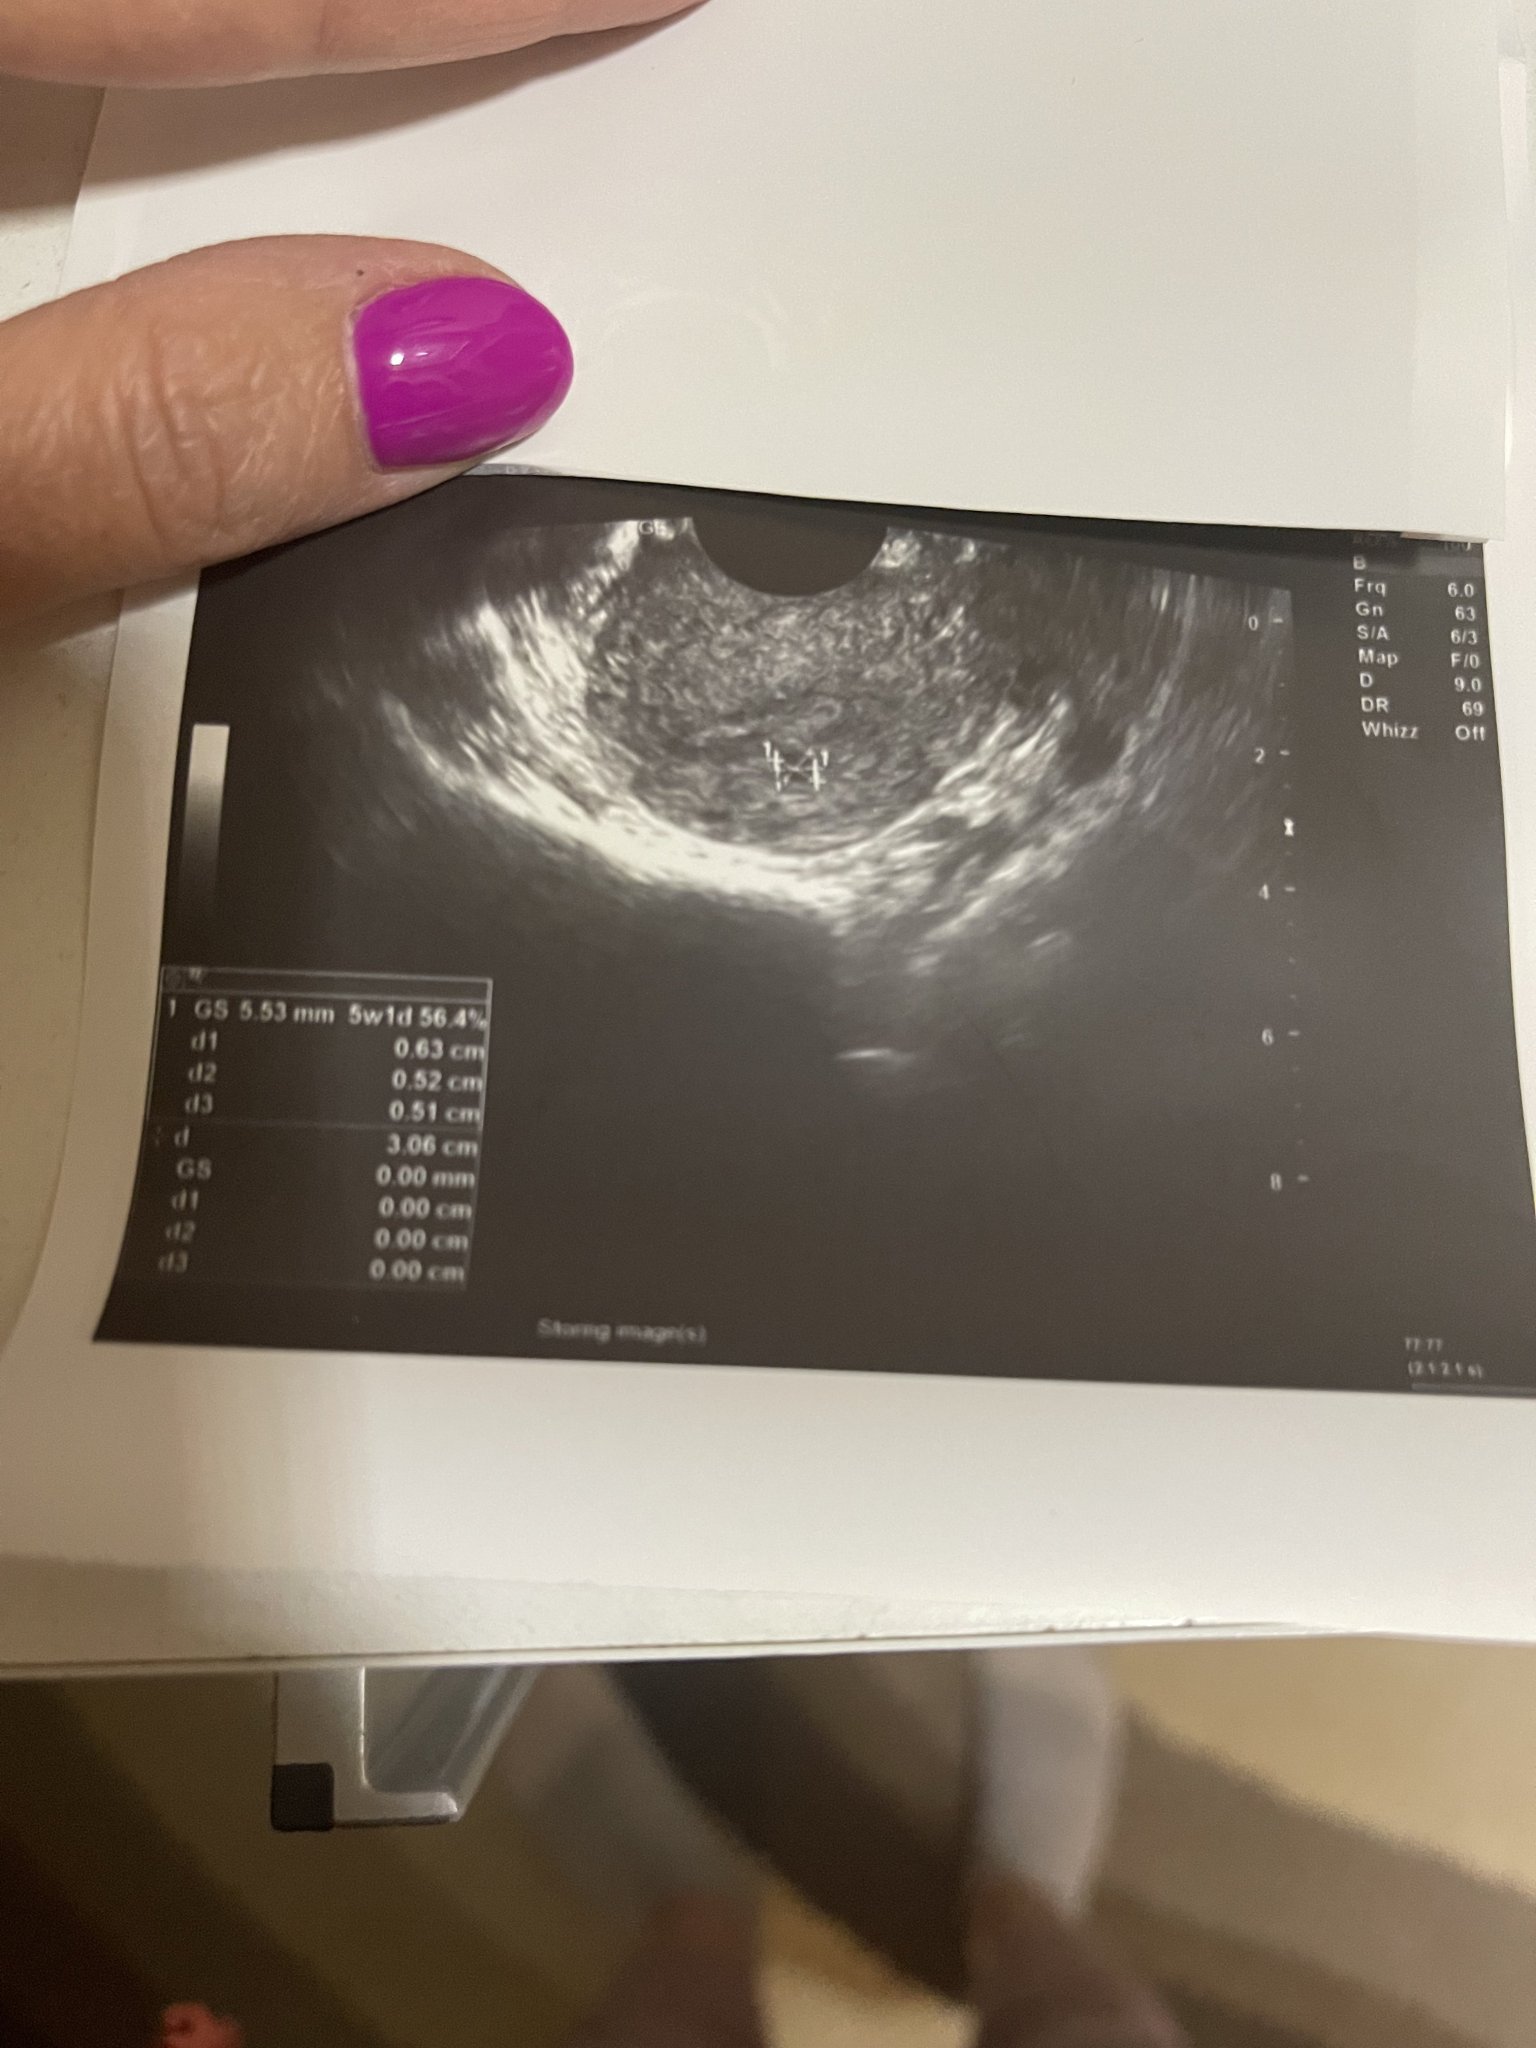

Аз пак съм в тъмни мисли и отчаяние. Днес поради болки ниско долу отидох в спешен кабинет  в столична болница, защото доктора ми не е на работа уикенда и ме насочи натам. Отговор защо имам болки бе това, че имам сраствания, а в матката не виждат “хубава” бременност. Ще приложа снимки на това, което виждат и не знаят какво е. Казаха ми да направя ново ЧХГ, но в тази лаборатория методиката им е друга и има разминаване в стойностити от лабораторията, където пусках всички останали. Нямам кървене, имам симптоми, имам и много объркващи мисли какво се случва, извънматочна бременност, биохимична или какво?!..

Пусни след два дни пак ЧХГ. На снимката все пак се вижда точка, при мен беше такава. После се превърна в малко ембрионче с пулсиращо сърчице и вече съм в 10 г. с. Не искам да ти давам фалшиви надежди, но защо да не е тая точица бъдещото ти бебче?

при тази ниска стойност на ЧХГ не се визуализира бременност все още, обикновено това става след 1000. Сигурно има и изключения, но това като цяло е информацията, която имам от АГ и от нета. И все пак проследете наистина ЧХГ след още 2 дни. Обикновено в началото нараства доста бързо и до 10ина дни закъснение достига четирицифрени стойности.

При мен нещата приключват, днес бях на преглед отново понеже се появи зацапване и болки. Плоден сак видяха(отговаря на 5г.с.) много ниско до разреза на предишната операция, но ЧХГ се е понижило до 49.88. Сега ми остана да чакам цикъл или ако прокървя да отида веднага.